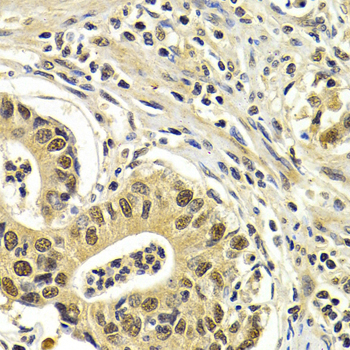

Immunohistochemistry of paraffin-embedded human normal stomach using CDK7 antibody at dilution of 1:200 (400x lens).